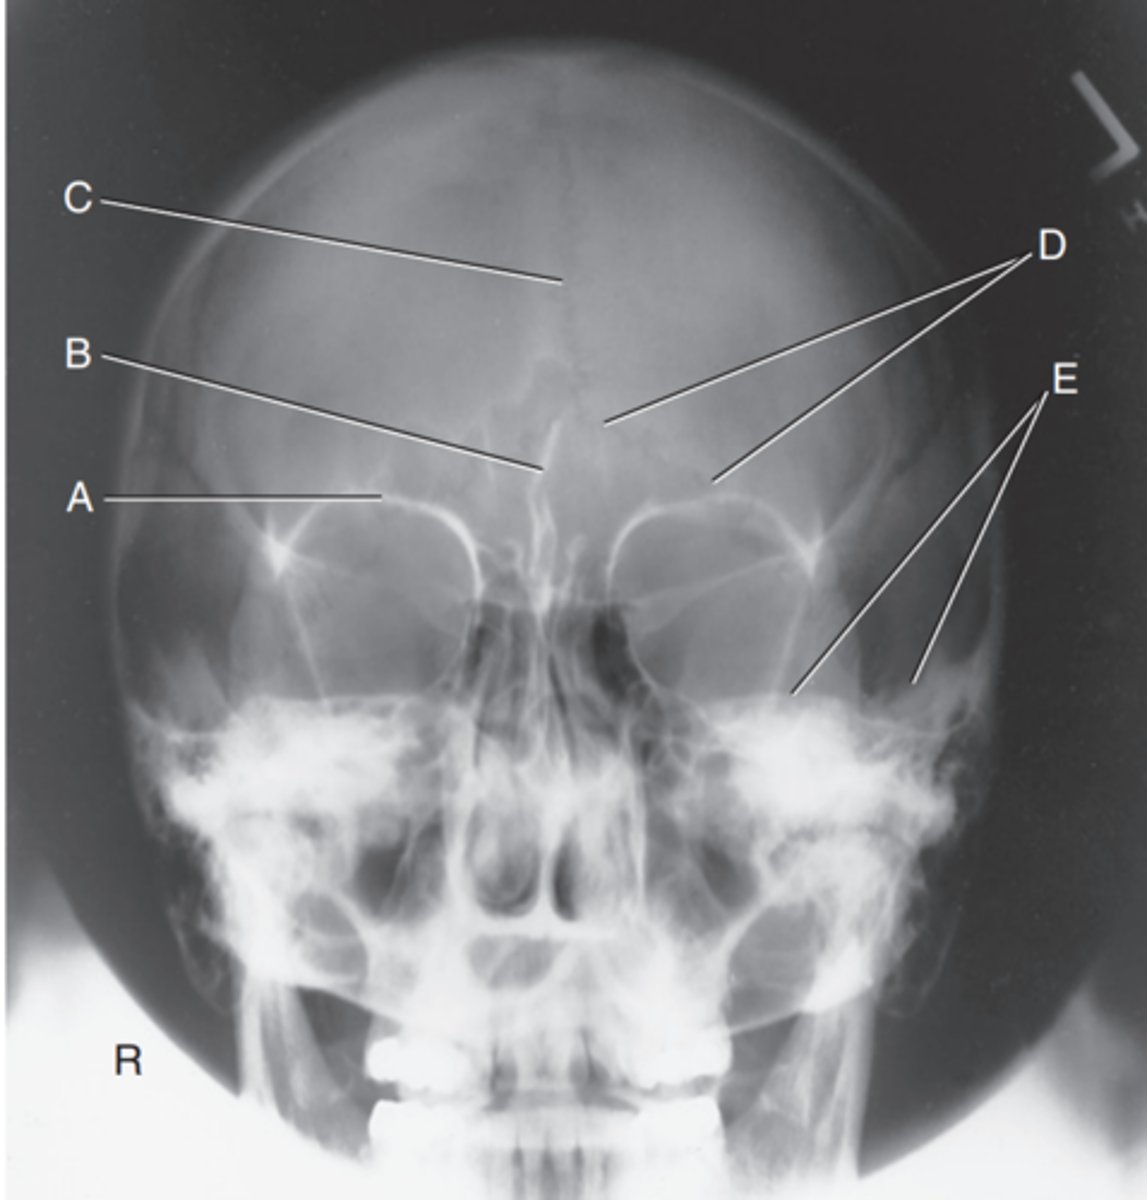

Supraorbital margin of right orbit

Label A

Crista galli of ethmoid

Label B

Sagittal suture

Label C

Lambdoidal suture

Label D

Petrous ridge

Label E